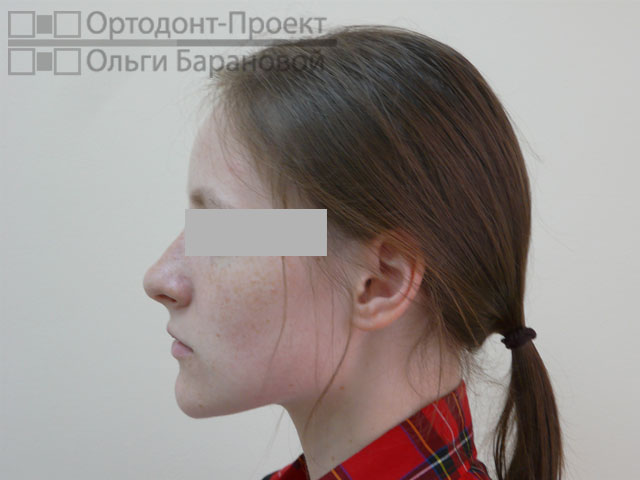

Проблема: к ортодонту О.А. Барановой обратилась молодая девушка с жалобами на то, что криво растут зубы.

Решение: выполнено лечение с удалением зубов, наиболее эффективное в данном случае. Для лечения использованы металлические брекеты Damon.

Ортодонт О.А. Баранова провела осмотр и рассказала о возможностях ортодонтического лечения. Возможны два варианта лечения при скученности зубов – с удалением или без удаления зубов. В «ОРТОДОНТ-ПРОЕКТЕ Ольги Барановой» редко используется удаление зубов, но в данном случае, при сильной скученности зубов и тонком биотипе пародонтальных тканей, у девушки ещё есть полноценные «восьмерки», поэтому все признаки за лечение с удалением. В данном случае лечение с удалением зубов приведёт к максимально грамотному, эстетичному и стабильному результату.

Фотометрия перед ортодонтическим лечением:

По результатам исследований и консультаций ортодонт О.А. Баранова составила план лечения, с которым ознакомила пациентку на второй консультации. Расчеты снимков показали, что вариант с удалением зубов предотвратит проблемы с десной и костной тканью челюстей, чреватые выхождением корня зуба за пределы кортикальной пластины и позволит достаточно быстро выровнять зубы.

Диагноз ортодонта: скученность фронтальной группы зубов верхней и нижней челюсти, сужение и укорочение верхнего и нижнего зубных рядов. Окклюзия нормальная.

Вторая причина — протрузия (выступание передних зубов). Зубы обеспечивают поддержку мягких тканей — щек, губ. При выраженном наклоне передних зубов мы часто наблюдаем «выпуклый» профиль. Иногда пациенту даже сложно сомкнуть губы. Удаление зубов в данном случае является абсолютно оправданной мерой для изменения положения зубов и улучшения эстетики лица.